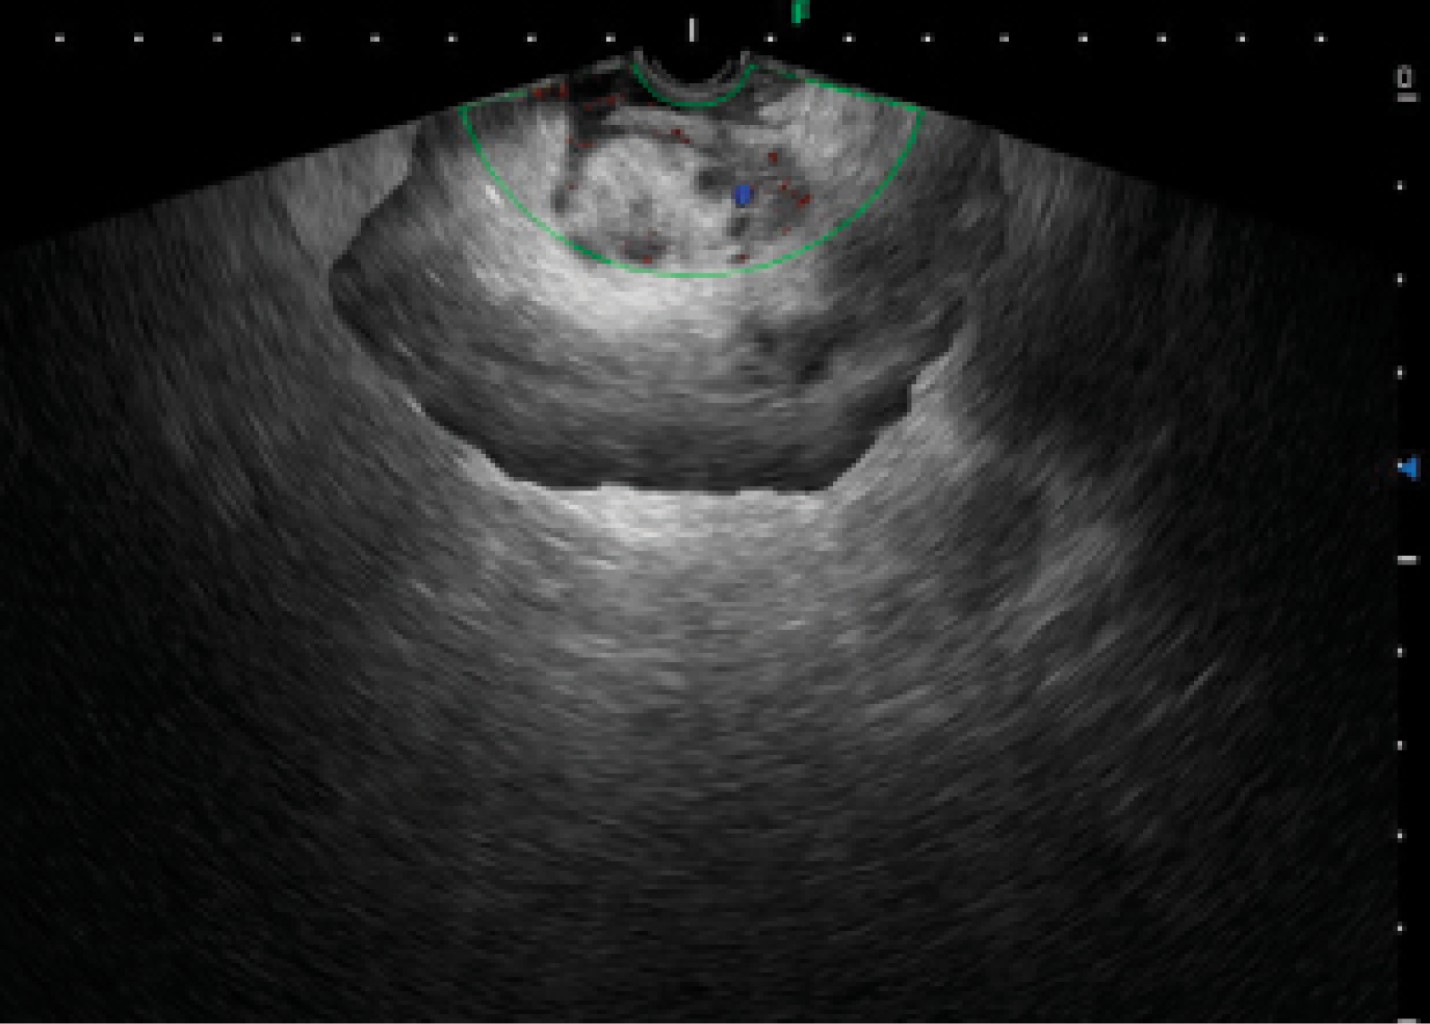

Introducción: La prevalencia de cáncer gástrico en México ha tenido un incremento en los últimos años con predominio en hombres. Los factores de riesgo son el consumo de alcohol, tabaco e infección por Helicobacter pylori, considerado en nuestra población como de riesgo moderado. Aunque el adenocarcinoma sigue predominando como la neoplasia maligna gástrica más frecuente, un porcentaje no despreciable del 7-8%, según la Organización Mundial de la Salud, lo ocupa el linfoma no Hodgkin (extranodal) y los leiomiosarcomas. El adecuado abordaje diagnóstico y la diferenciación son cruciales entre el adenocarcinoma y el linfoma, ya que de ello depende el pronóstico y el tratamiento. Caso clínico: Se comunica el caso de un hombre de 79 años con astenia, hipercalcemia maligna con hallazgo incidental de engrosamiento gástrico por tomografía. Se realizó ultrasonido endoscópico para el diagnóstico de linfoma gástrico de variedad difuso (Ann Arbor modificada II2). Revisión de literatura: El ultrasonido endoscópico es considerado una herramienta para el diagnóstico de neoplasias malignas gástricas en todas sus variantes, principalmente donde la enfermedad se encuentra en capas profundas. Conclusión: El ultrasonido endoscópico es el método que nos lleva a obtener alta precisión diagnóstica en linfoma gástrico permitiendo la toma de biopsias del espesor total de la pared de bloque celular para realizar diagnóstico diferencial siempre con inmunohistoquímica.

Figura 2